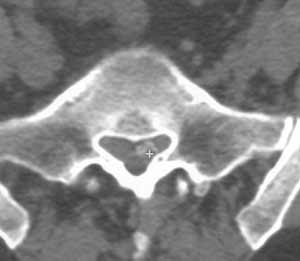

Рис 2. Обызвествленная пролабированная часть диска L5-S1 в правом латеральном кармане. (Слева) Имеет пониженную интенсивность при GRE  последовательности (стрелка). (Справа) Обызвествление хорошо видно на КТ.